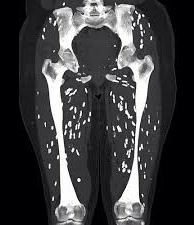

Цистицеркоз диагностируют при помощи УЗИ, рентгена, КТ, МРТ и биопсии. На УЗИ хорошо видно кисту и сколекс цистицерка в мышцах и подкожной клетчатке. На рентгене видно кальцификаты. КТ и МРТ полезны для определения точного расположения цистицерка. На КТ лучше видны мелкие кальцинаты. На МРТ лучше видно сколекс и кисту.

| Фото. А, Б На рентгене и КТ хорошо видно кальцификаты в мышцах и подкожной клетчатке очаги по типу зерен риса по ходу мышечных волокон это цистецерки в мышцах и коже; В На МРТ хорошо видны цистицерки в головном мозге, зрительном нерве (стрелка), в глазных мышцах белые округлые кисты с черным сколексом внутри. | ||||||||||||||||||||||||||||||||||||||||||